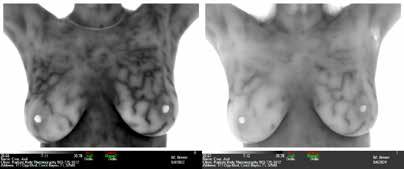

Breast Screening

EMERALD COAST THERMOGRAPHY

Located in Miramar Beach & Gulf Breeze 850-980-1005

EmeraldCoastThermography@gmail. com EmeraldCoastThermography.com

We are passionate about educating people on the importance of routine health screenings using 100% radiationfree, touch-free, state-of-the-art infrared cameras. Call or email us for more information; you may also book your appointment online. See ad, page 6.

RADIANT BODY THERMOGRAPHY

Candace Parmer Clinical Thermographic Technician 503-775-1812

RadiantBodyThermography.com

Call to learn how we can assist you and your doctor in protecting breasts from disease, excess hormonal activity and over diagnosis of breast cancer. See ad, page 11.